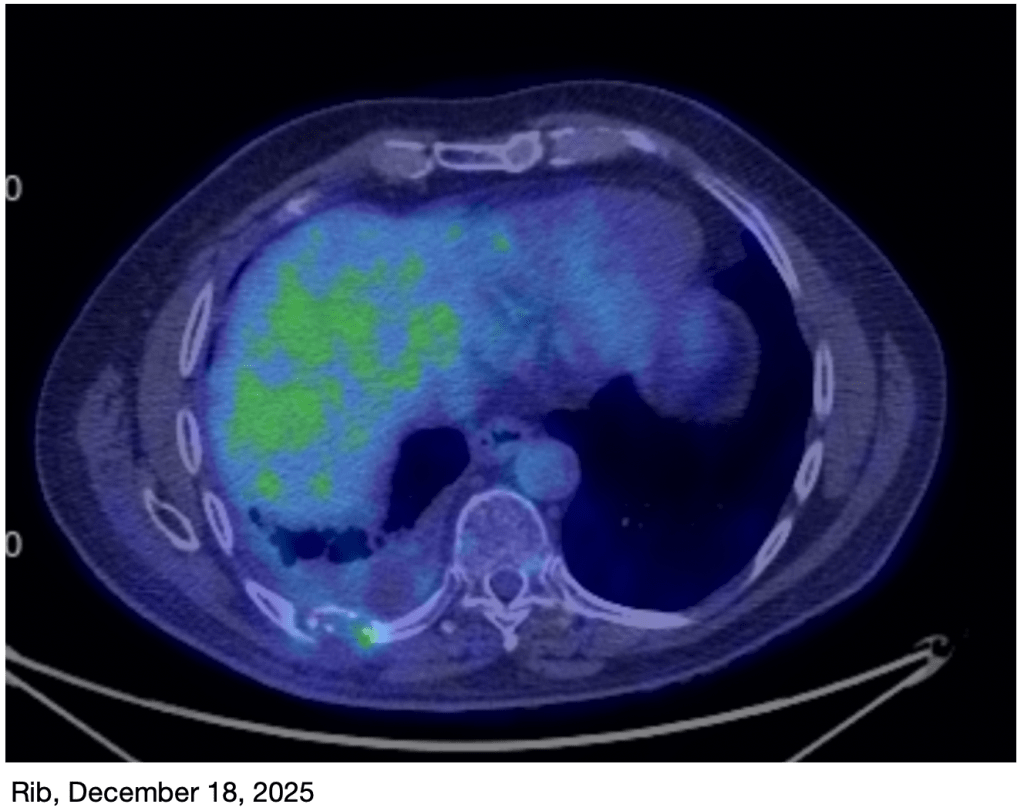

Until about a month ago, my pain was gradually increasing as my new tumors grew. Happily, my new treatment regimen is apparently working! For the last month or so, my pain level has been decreasing, allowing me to tune down my pain meds. Additionally, a PET scan just yesterday revealed that the new tumors, which weren’t responding to the old treatment regimen, are responding well to the new one.